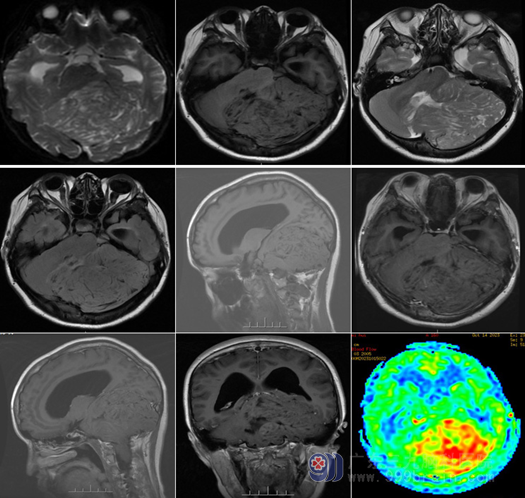

查体 :神志清醒,双侧眼球震颤,瞳孔不等,右侧瞳孔 3mm,直接间接对光反射灵敏,左侧瞳孔 4mm,直接间接对光反射迟钝,双眼视力显著下降,双侧视野缩窄,双侧鼻唇沟对称,伸舌偏左,闭目难立征阳性,一字步征阳性,指鼻试验阳性。头部 MR 提示 :左侧小脑半球 - 脑干巨大占位病变,继发枕骨大孔疝、幕上梗阻性脑积水,考虑小脑发育不良性神经节细胞瘤,左侧颞部蛛网膜囊肿,左侧小脑上动脉、小脑前后下动脉远端分支增多,MRV未见明显异常。听觉诱发电位 :左耳 80db 未引出,右耳80db 可引出。听力测试 :左耳 97db,右耳 30db。

头颅MR:左侧小脑、左侧桥臂示巨大团块状占位,呈等T1等变,原病变已大部分切除。T2、FLAIR序列等高异常信号影,间杂多发长T1长T2、FLAIR序列低信号影,DWI序列呈等稍高信号,ADC图呈等高信号,增强后可见散在线样强化影;病变往椎管内生长达C2椎体水平,邻近脑组织受压变形,小脑幕受压上抬。

MRI 是诊断 LDD 的可靠方法,并且能指导治疗方案的制定。肿瘤在 MRI T1 加权像上表现为低信号,在 T2 加权像上表现为沿小脑皮质走行的高低信号相间的条纹状结构,即“虎纹征”——此为典型影像学特征。DWI 高信号和表现弥散系数 (apparent diffusion coefficient,ADC) 下降。肿瘤 PWI 高灌注和 MRI 增强扫描无强化也是诊断 LDD 的重要指标。